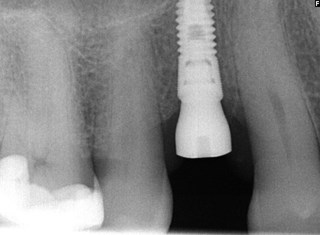

Titanskruven - fixturen är på plats och kommer att integreras med käkbenet